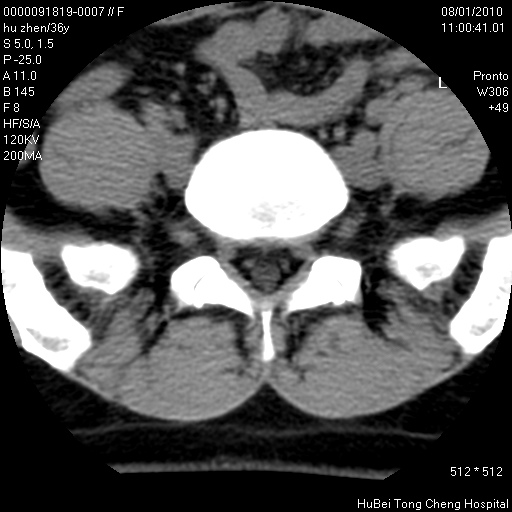

患者 女,36岁。右侧腰腿痛半月余。腰骶椎mr平扫偶然发现骶椎异常信号。

临床诊断:1)腰椎间盘突出症。2)骶椎肿瘤性病变?

骶椎ct平扫(层厚、层距均为5mm),图像如下:

良性骨病变,骨纤还是骨母细胞瘤?

考虑s1骨纤维异常增殖症。

骨良性病变、成骨细胞瘤